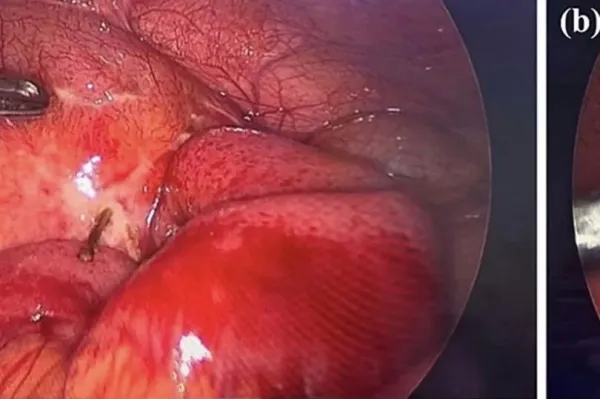

The medics then ordered an emergency laparoscopy to investigate further, and that's when they found the cause: a wooden toothpick, which had perforated the bowel, as reported by NeedToKnow.

Doctors were able to remove it from the bowel, and noted the area had already sealed over, leaving them to apply surgifoam [a sterile sponge used to control bleeding] to the extraction site.

The rest of the area was examined but thankfully the toothpick hadn’t caused any further damage.